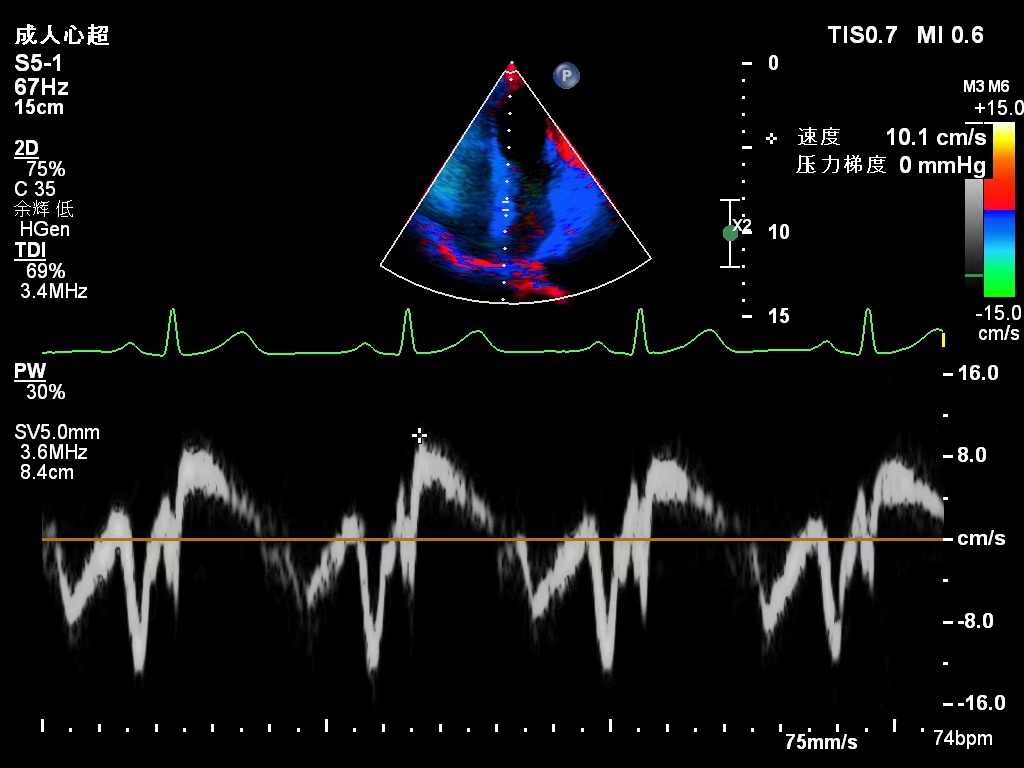

超声波携带能量(声能)并可传至传播物体,传播物体的回声(反射声)中包含传播物体的声学物理信息,利用特殊的接收装置将这些信息转换成可见的图像,就形成了我们平常见到的超声检查图像(不好理解看上图),能较为清晰的显示人体的内部结构及其变化情况,以此来判断有无病态变化的产生及异常物质的存在。